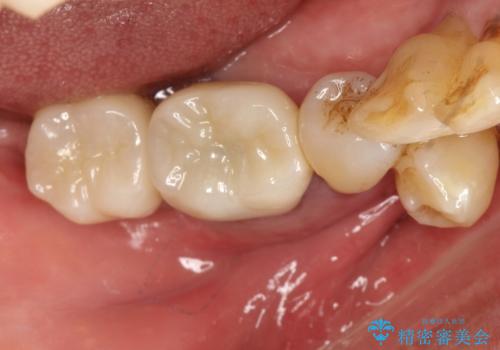

[歯周病治療] 歯周補綴 インプラント補綴

![[歯周病治療] 歯周補綴 インプラント補綴の症例 治療前](https://seimitsushinbi.jp/wp/wp-content/uploads/2020/03/067ed603e15bc4c623e950ffbd6c0829-500x350.jpg?v=1585493851)

![[歯周病治療] 歯周補綴 インプラント補綴の症例 治療後](https://seimitsushinbi.jp/wp/wp-content/uploads/2020/03/93a1bf8bd8e0f11621dbb40f6f1d795c-500x350.jpg?v=1585494318)